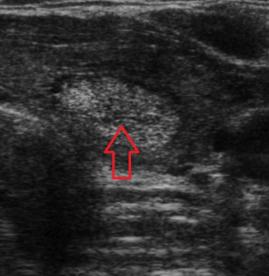

- Tiroid iltihabı (Hashimoto)

- Hashimato'da lazer tedavisi: İlaç dozlarının azaltılması veya kesilmesi ve kilo kontrolü !!!

- Hashimoto hastalığında destek tedavileri